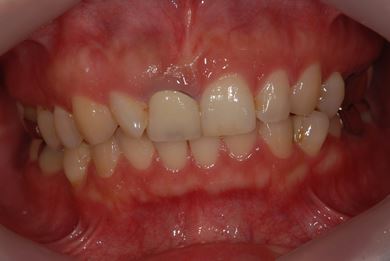

| 性別/年齢 | 女性 / 38歳 | ||||||||||||||||||||||||||||||||

| 主訴 | 右奥歯2本、インレーの相談をしたい。 | ||||||||||||||||||||||||||||||||

| 治療方針 | セラミック治療にて、審美的回復を行う。 | ||||||||||||||||||||||||||||||||

| 治療内容 | ハイブリッドセラミックインレー2本、メタルボンドセラミッククラウン2本(メタルボンド用土台2本)、オールセラミッククラウン1本(オールセラミック用土台1本) | ||||||||||||||||||||||||||||||||